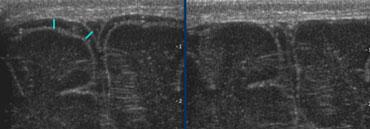

Flaring

Thuật ngữ flaring được dùng để mô tả các vùng quanh não thất có hồi âm tăng nhẹ, thường gặp ở nhiều trẻ sinh non trong tuần đầu tiên của cuộc đời.

Trong tuần đầu này, chưa thể xác định chắc chắn đây là biến thể bình thường hay là dấu hiệu của PVL độ 1.

Flaring tồn tại kéo dài sau tuần đầu tiên của cuộc đời được định nghĩa là PVL độ 1.

TRÁI: Hình ảnh khảo sát ban đầu cho thấy flaring. PHẢI: Hình ảnh tái khám sau một tuần cho thấy chất trắng quanh não thất bình thường.

Cần theo dõi tái khám để phân biệt flaring với PVL độ I.

Trường hợp bên trái minh họa một trẻ sinh non có hình ảnh flaring.

Tại lần tái khám, không ghi nhận sự hình thành nang và sau tuần đầu tiên, chất trắng quanh não thất trở về hình ảnh bình thường.